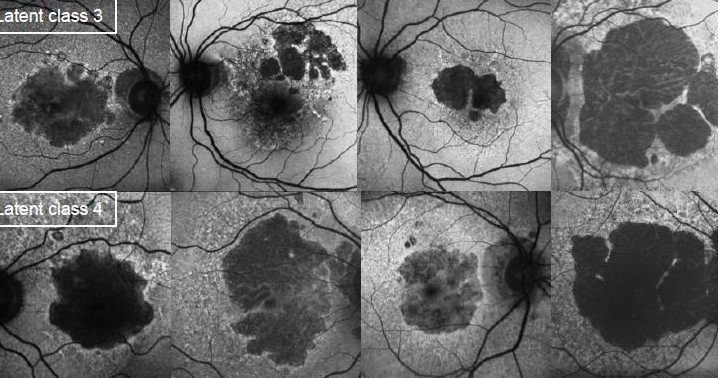

Reappraisal of geographic atrophy patterns seen on fundus autofluorescence using a latent class analysis approach. 20/11/2014

Biarnés M, Forero CG, Arias L, Alonso J, Monés J. Invest Ophthalmol Vis Sci. 2014 Nov 18;55(12):8302-8. doi: 10.1167/iovs.13-13542 http://1.usa.gov/11G5LIC

DMAE exudativa o húmedaAutofluorescencia